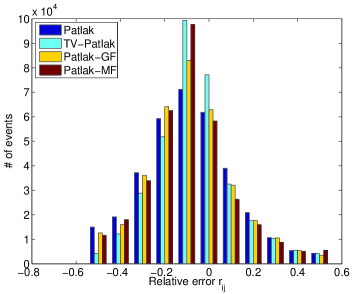

In the images shown in the figures we illustrate the calculated uptake rates of the FDG. Images for the CMRGlc can be obtained by directly scaling . In figure 1 we compare the result of using Patlak and TV-Patlak for estimating the uptake rates with respect to no noise, noise in the input function, Poisson noise in the sinogram, and finally with respect to the case in which the irreversibility assumption is violated but without noise in the sinogram or input data. In each case the histogram of the relative errors is given on the left, the Patlak image in the middle and the TV-Patlak on the right. The different scales in the histograms are due to the total number of results illustrated. When there is no noise (triples and ) the histogram illustrates results over all voxels but only one simulation, while for the noisy simulations the results are for all voxels over all realizations of the noise. The TV-Patlak images are more homogeneous in all cases and the relative errors are smaller. The figures clearly show the improvements of employing the TV-Patlak method as compared to using Patlak independently for each voxel. This is confirmed in figure 2 in which images with noise in the sinogram, positive and different noise levels in the input function are shown.

Quantitative measurements, confirming the illustrations, are presented in table 3. There we also present the results for conventional Patlak’s method with post-smoothing by two standard filters:

Consistent with the observation in [21, 16], we find that violation of the Patlak assumption, , introduces about bias; when but for . The rows (std) and “# 10% (#15%)” provide complementary supporting information, indicating that the TV is minimized by TV-Patlak; as compared to Patlak, Patlak-GF and Patlak-MF the number of voxels with larger error is reduced. In particular, we emphasize that TV-Patlak provides a better noise removal mechanism than popular post-filtering approaches.

In figures 3 and 4 we illustrate the uptake rates and relative error in the uptake rates, respectively, calculated by Patlak, TV-Patlak, Patlak-GF and Patlak-MF for one simulated data case , i.e. , noise in the input function and Poisson noise in the sinograms. The uptake rate image generated by Patlak-MF is visually smoother than that by TV-Patlak, but the equivalent histograms show that the relative error is higher for Patlak-MF than for TV-Patlak; the Patlak-MF image is over-smoothed.